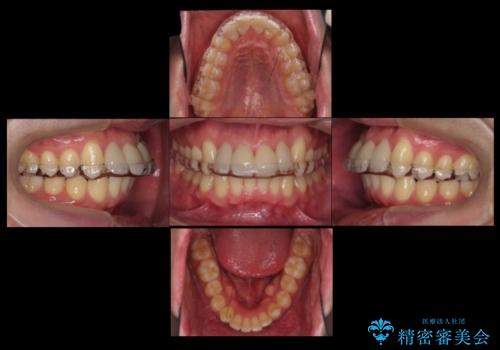

- 前歯のすき間を気にして来院。

矯正治療か、セラミックで最短で治すかの選択肢を提示し、セラミックで治すことにしました。

利点は、早く終わる上に、保定の必要がないため負担が少ないことが挙げられます。

ただし、セラミックは欠ける特性があるため、夜はナイトガードを使用していただくことにしました。

全て神経は取らずに、削りました。

長年コンプレックスだったすき間が閉じたとのことで、喜んでいただきました。